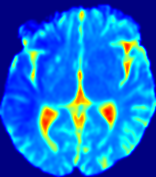

4.3.2 Diffusion Imaging via Advection-Diffusion

Slice #1Slice #2Slice #3Slice #4Slice #5Slice #6Dgtsuperscript𝐷gtD^{\text{gt}}Refer to captionRefer to captionRefer to captionRefer to captionRefer to captionRefer to captionDestsuperscript𝐷estD^{\text{est}}Refer to captionRefer to captionRefer to captionRefer to captionRefer to captionRefer to captionRefer to caption0.300.300.300.240.240.240.180.180.180.120.120.120.060.060.060.000.000.00(mm2/s)𝑚superscript𝑚2𝑠(mm^{2}/s)𝐕est𝟐subscriptnormsuperscript𝐕est2\|\bf{V}^{\text{est}}\|_{2}Refer to captionRefer to captionRefer to captionRefer to captionRefer to captionRefer to captionRefer to caption0.00300.00300.00300.00240.00240.00240.00180.00180.00180.00120.00120.00120.00060.00060.00060.00000.00000.0000(mm/s)𝑚𝑚𝑠(mm/s)

Figure 15: PIANO identifiability testing: diffusion imaging via advection-diffusion. Top row shows Dgtsuperscript𝐷gtD^{\text{gt}} used for simulating ground truth pure diffusion. Rows below show the estimated Destsuperscript𝐷estD^{\text{est}} and 𝐕est2subscriptnormsuperscript𝐕est2\|{\bf{V}}^{\text{est}}\|_{2} on corresponding slices. Note that the plotted value scale for 𝐕est2subscriptnormsuperscript𝐕est2\|{\bf{V}}^{\text{est}}\|_{2} is 0.01 of that for Dgtsuperscript𝐷gtD^{\text{gt}} and Destsuperscript𝐷estD^{\text{est}}.

Similarly, we test the behavior of PIANO when estimating both advection and diffusion from a pure diffusion-driven process. The goal is to determine if PIANO is able to recognize that there is only diffusion governing the given concentration time-series. We use the same ‘Diffusion Imaging’ data simulation of Sec. 4.2.1 as the concentration dataset, PIANO estimates both velocity 𝐕estsuperscript𝐕est{\bf{V}}^{\text{est}} and diffusivity Destsuperscript𝐷estD^{\text{est}}. Estimation results in Fig. 15 confirm PIANO’s identifiability again: the estimated 𝐕est2subscriptnormsuperscript𝐕est2\|{\bf{V}}^{\text{est}}\|_{2} is almost invisible compared to Destsuperscript𝐷estD^{\text{est}}, even plotted with a 1%percent11\% value range compared to that for Destsuperscript𝐷estD^{\text{est}}. On the other hand, Destsuperscript𝐷estD^{\text{est}} achieves comparable estimation performance as ‘Diffusion Imaging via Diffusion’ in which PIANO predicts Destsuperscript𝐷estD^{\text{est}} alone (shown in Fig. 13).